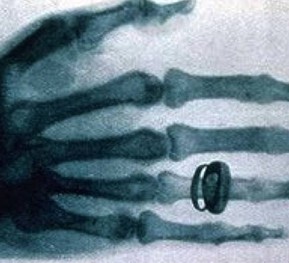

X光機主要是由X光機電源,X光球管以及控制電路等組成,是產(chǎn)生X光的設備,目前已廣泛應用于醫(yī)院協(xié)助醫(yī)生診斷疾病,工業(yè)的無損探傷,科學教育,機場和火車站的安全檢查等

圖像監(jiān)控法是直接從x射線透視圖像構(gòu)形來判斷物品的,因此,被檢物是否可疑,取決于監(jiān)視器或顯示器上的圖像。顯示器或監(jiān)視器上出現(xiàn)的不常見物或異形物,都應視為可疑物品。那些不能準確辨認的物品也應視為可疑物品,需仔細觀察,根據(jù)需要可將圖像定位分析。